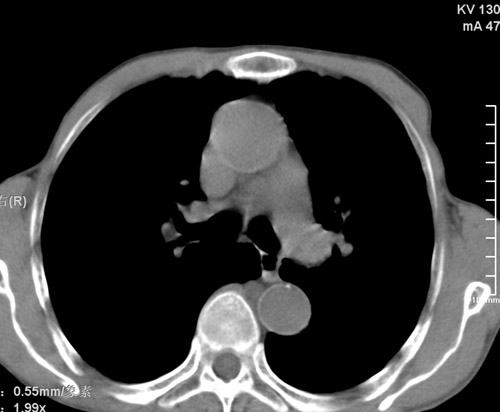

标题: CT17529:男 76 胸背部不适半月 胸透支气管炎 行CT检查 [打印本页]

标题: CT17529:男 76 胸背部不适半月 胸透支气管炎 行CT检查

意见 老年肺 少许炎症 肺大泡 右肺门略大 但支气管通畅  请各位高手指教如何下意见

支持楼主意见,右肺门略大,可能为肺动脉增粗.

慢支肺气肿,肺动脉高压.